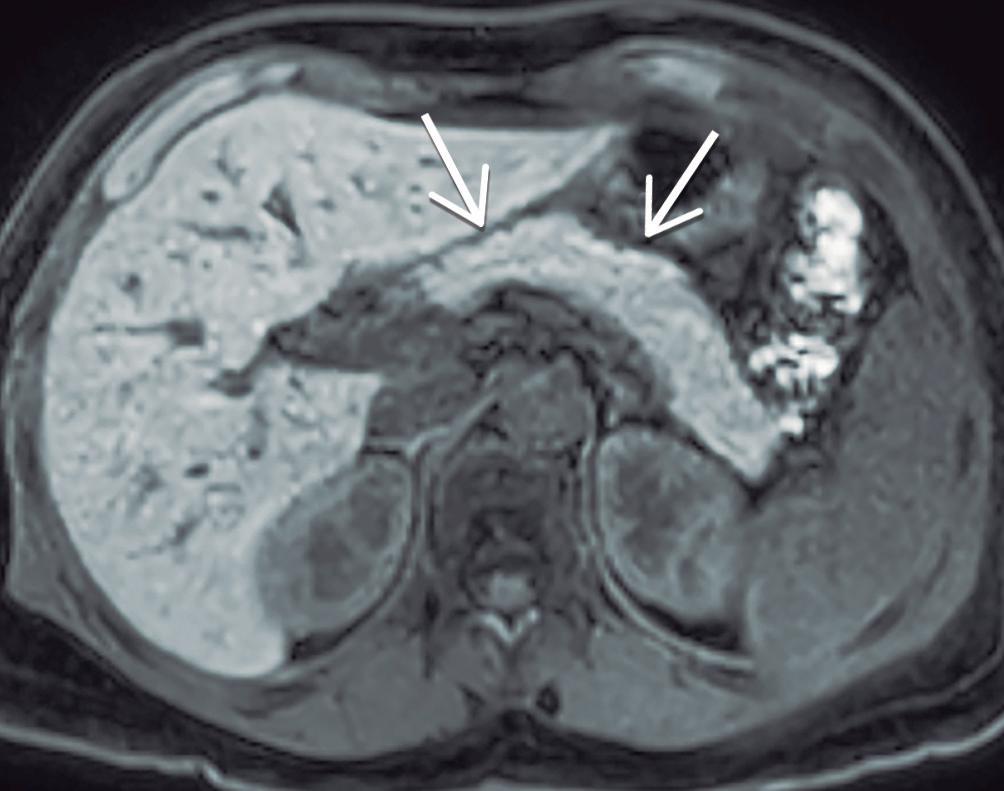

Manifestaciones extra-pancreáticas en PAI 1

Considerando que la PAI tipo 1 es la manifestación pancreática del compromiso sistémico por IgG4, el compromiso de otros órganos es un sello distintivo y un criterio decisivo en el diagnóstico de la enfermedad.

Colangiopatía IgG4

La vía biliar es el sitio más frecuentemente afectado, con una prevalencia reportada de 60 a 85% de los pacientes. En la enorme mayoría de los casos existe también compromiso del páncreas, muy excepcionalmente puede presentarse colangiopatía IgG4 sin afectación pancreática. Los sectores comprometidos de la vía biliar muestran engrosamiento parietal circunferencial, difuso, de segmentos relativamente prolongados. Exis-

te moderado a intenso realce post-contraste de las paredes de los conductos involucrados y en la RM con secuencias de difusión suele observarse restricción. El conducto colédoco distal intra-pancreático es el sector que se ve involucrado con mayor frecuencia y conlleva una dilatación leve a moderada de la vía biliar proximal, condicionando la típica presentación clínica de ictericia obstructiva que suelen tener estos pacientes. Las manifestaciones radiológicas pueden asemejarse a la CEP, pero existen sutiles diferencias que contribuyen a su distinción. En la CEP predomina el compromiso de la vía biliar intrahepática, las estenosis son más cortas y alternan con dilataciones saculares múltiples, conformando un patrón tipo “cuentas de rosario” o “árbol podado”, en contraposición de las estenosis largas y continuas de la colangiopatía IgG4.23-26

El compromiso predomina en la vía biliar extrahepática, principalmente la porción intra-pancreática del conducto colédoco, existiendo también, en menor medida, afectación de la vía biliar intrahepática. Existe un engrosamiento circunferencial difuso de las paredes de los ductos biliares en segmentos relativamente prolongados, con bordes lisos, de aspecto “ahusado”. Las paredes de los conductos afectados tienen característicamente una señal hipointensa en T2 y realzan intensamente post-contraste intravenoso. El diagnóstico imagenológico diferencial se realiza con la colangitis esclerosante primaria (CEP), donde las estenosis son más cortas, intercalándose dilataciones focales irregulares, de segmentos menos prolongados, adoptando un patrón tipo cuentas de rosario. 11a. Colangio-RM: Estenosis biliares largas, de bordes lisos, con leve dilatación ductal proximal a las mismas. 11b. Secuencia T1 con contraste, fase portal: Engrosamiento circunferencial, difuso, con intenso realce post-contraste intravenoso involucrando el conducto hepático común y las ramas intrahepáticas. 11a 11b

Figura 11. Colangiopatía IgG4